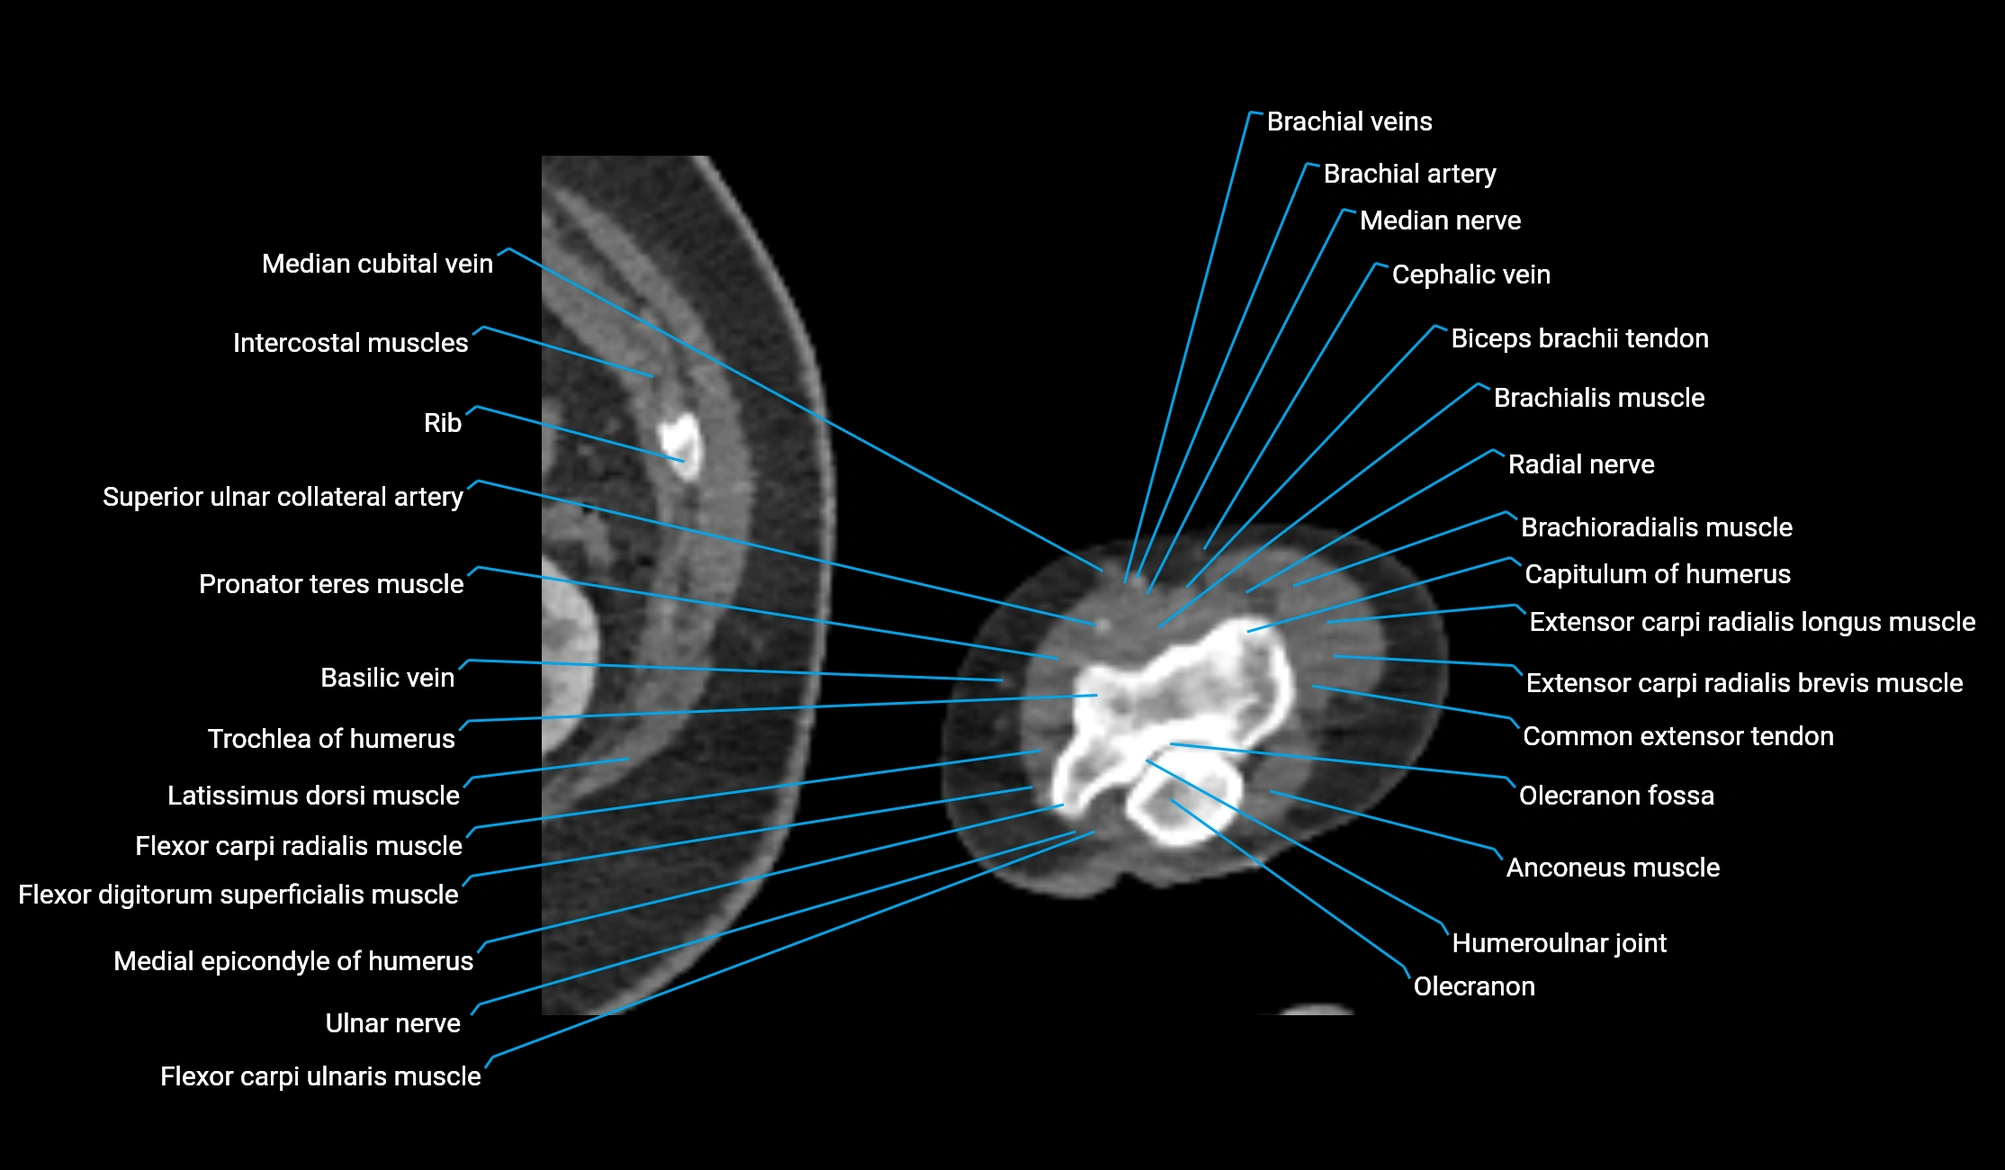

CT image